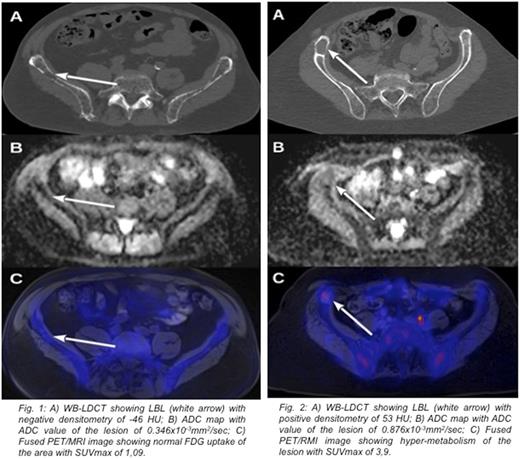

Results: A hundred thirtyfive lytic >5 mm diameter bone lesions were recognized by WB-LDCT in patients under study. Thirtyfive lesions (mean dimension 11,09 SD ± 1,5 mm) had a negative densitometry (mean -57,57 HU; SD ± 33,13 HU) showing high signal in T1w images, low signal in STIR and DWI sequences, while 100 lesions (mean dimension 17,36 SD ± 2,64) presented positive densitometry (mean 44,87 HU; SD ± 23,89) showing low T1w signal and high signal in STIR and DWI sequences. The first group presented low ADC values (mean 0,360x10-3 mm2/sec; SD ± 0,154) and low SUV max values (mean 1,69; SD ± 0,56), while the second group showed higher ADC values (mean 0,868x10-3 mm2/sec; SD ± 0,207) and SUV max values (mean 5,04; SD ± 1,94) (Fig. 1 and Fig.2). Mean ADC values and mean SUV max values between the two groups were statistically different (p value < 0,01). Eight patients presented positive and negative density LBL, 7 patients presented only positive density LBL and 3 patients presented only negative density LBL. In two patients of this latter group who did not start therapy, negative density LBL, became positive in conjunction with biochemical progression disease during the 12 months follow up. In terms of SUV and ADC a significant concordance was found between PET and MRI for both positive and negative densitometry LBL, (91% and 94%, respectively) considering a cut off value of SUV>2 and ADC>0,6 x10-3mm2/sec as abnormal. Finally, we showed a strong statistical correlation between positive densitometry LBL and ADC value >0,8 x10-3 mm2/sec, typical of focal lesion (58% vs. 2,86%, p<0,0001) and between positive densitometry LBL and SUV value >2 (92% vs. 2,86%, p<0,0001).

Conclusions: By measurement of internal densitometry, WB-LDCT differentiates two different patterns of lytic lesions: one characterized by fat replacement of trabecular bone (HU<0), likely expression of high osteoclastic activation, and one characterized by cell infiltration (HU>0). Both types of lesions can coexist in the same patient and were indicative of active disease, according to laboratory parameters. The observation that mean diameters of fatty LBL were significantly lower than that of proliferative LBL might suggest a particularly high cytokine/chemokine secreting PCs clone. Alternatively, fatty LBL might represent an early stage, which anticipates a massive infiltration by PCs. PET and MRI recognized only proliferative LBL, characterized by presence of pathological PCs within the lesion, whereas fat substitution of LBL led to a negative ADC and PET result. Then, if only PET/MRI had been evaluated, fatty LBL would have not been misleadingly considered as a proof of symptomatic disease. Especially in this subset of patients, WB-LDCT adds specific information, contributing to a proper definition of bone involvement in MM patients.